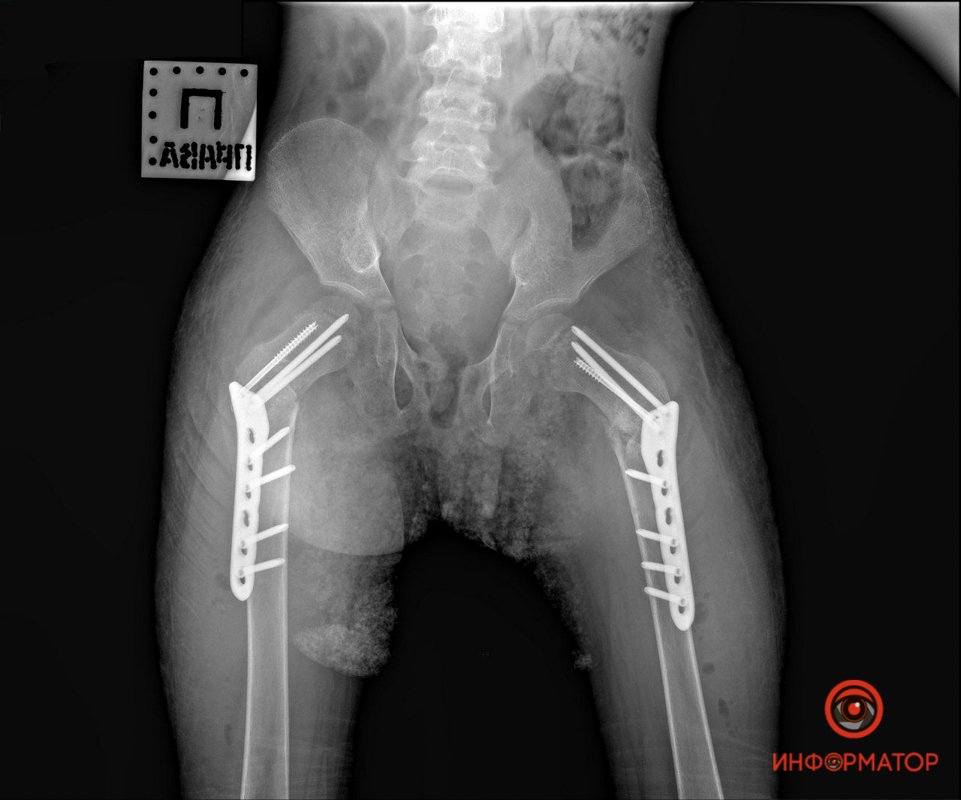

"9 мая к нам доставили мальчика с задержкой в развитии из Никополя. У ребенка случился эпилептический приступ, когда он сидел в "позе лотоса". Как следствие - сломал 2 шейки бедренной кости. Его прооперировали в пятницу по современной методике (открытая репозиция, остеосинтез LCP- пластиной) - сразу выполнено лечение двух бедер. Мальчик уже в палате, без гипсовых повязок, во вторник поедет домой", - рассказал Дмитрий Ершов.

Врач добавил, что обычно такие повреждения лечатся длительным скелетным вытяжением, после чего 2-3 месяца пациент должен пребывать в гипсовой повязке. Малыш же получил современное хирургическое лечение, после которого ему понадобится лишь реабилитация для возвращения способности к ходьбе. Случай такого лечения - крайне редкий, в мировой литературе есть лишь несколько подобных примеров, отмечает врач.